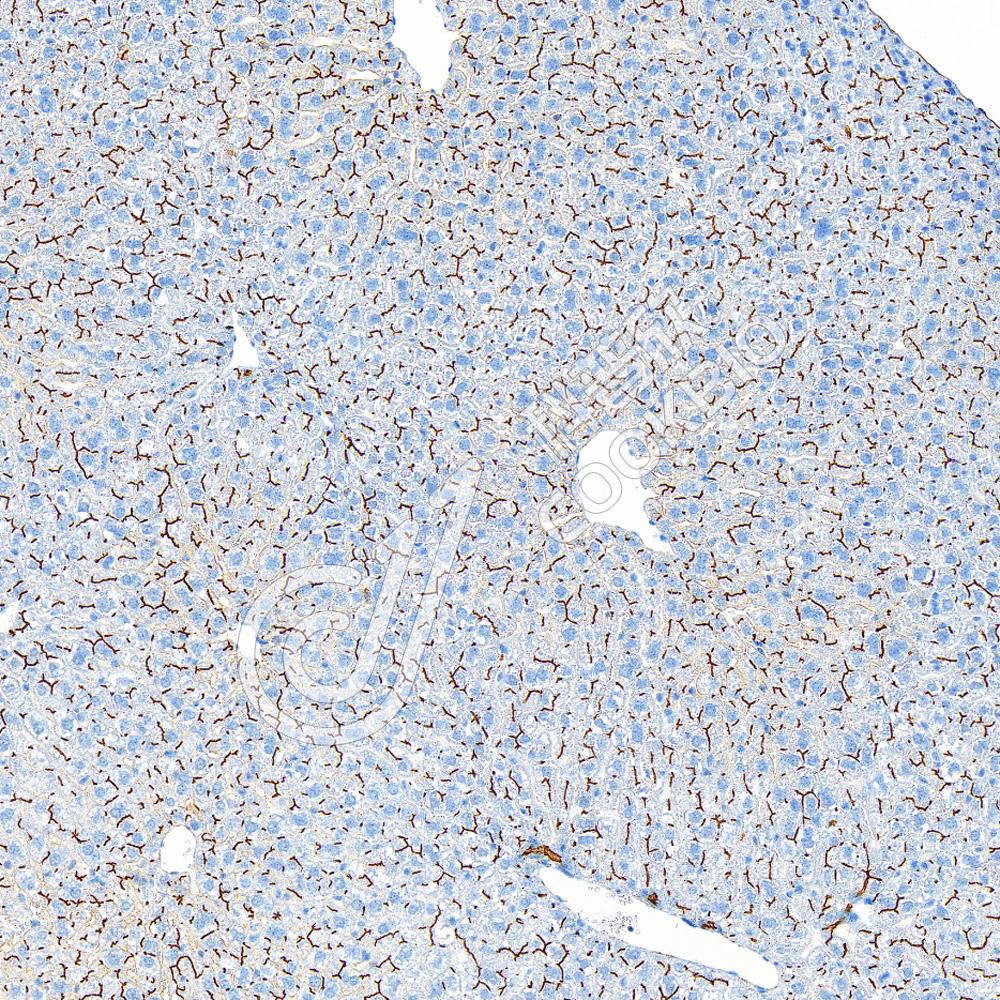

Recombinant Anti-P Glycoprotein antibody (兔单克隆抗体)

重组抗体,多耐药

WB

H,M,R

|

货号:K5467154-100

K5467154-100

IHC/IF

100 μL

¥ 1900